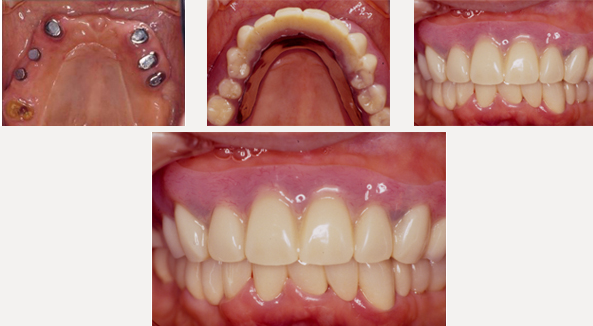

治療後

上顎は磁石義歯とし、インプラント磁石も追加し快適性を向上しました。 下顎は奥歯はインプラント治療、前歯はセラミックブリッジにて固定製にしました。

治療内容

- 磁石義歯

- インプラント磁石総義歯

- 再生治療

- インプラント(6本)

- セラミックブリッジ(8本)